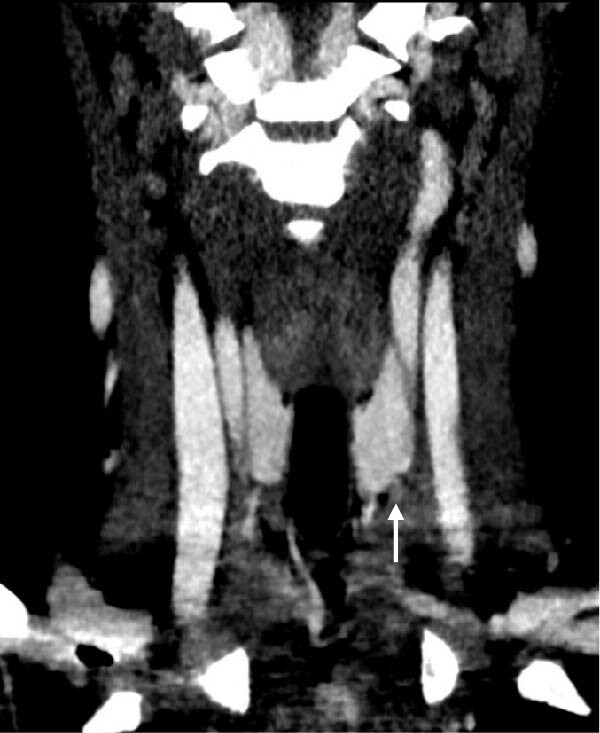

В то же время, во время сцинтиграфии паращитовидных желез с 99мТс-МИБИ не было отмечено накопления препарата. Далее была проведена четырехмерная компьютерная томография (4D КТ), которая не показала наличия глубоких узлов в средостении (рис. 8-11)). По результатам обследования был исключен синдром множественной эндокринной неоплазии (МЭН), хотя семья отказалась от генетического тестирования.

Рисунки 8-11. Снимки 4D КТ в поперечной (8,9), сагиттальной (10) и коронарной (11) плоскостях, где заметны слегка контрастируемые узелки в претрахеальной подкожной клетчатке (8-10) и в нижнем полюсе левой доли щитовидной железы (11). Размеры варьируют от 3 до 12 мм.